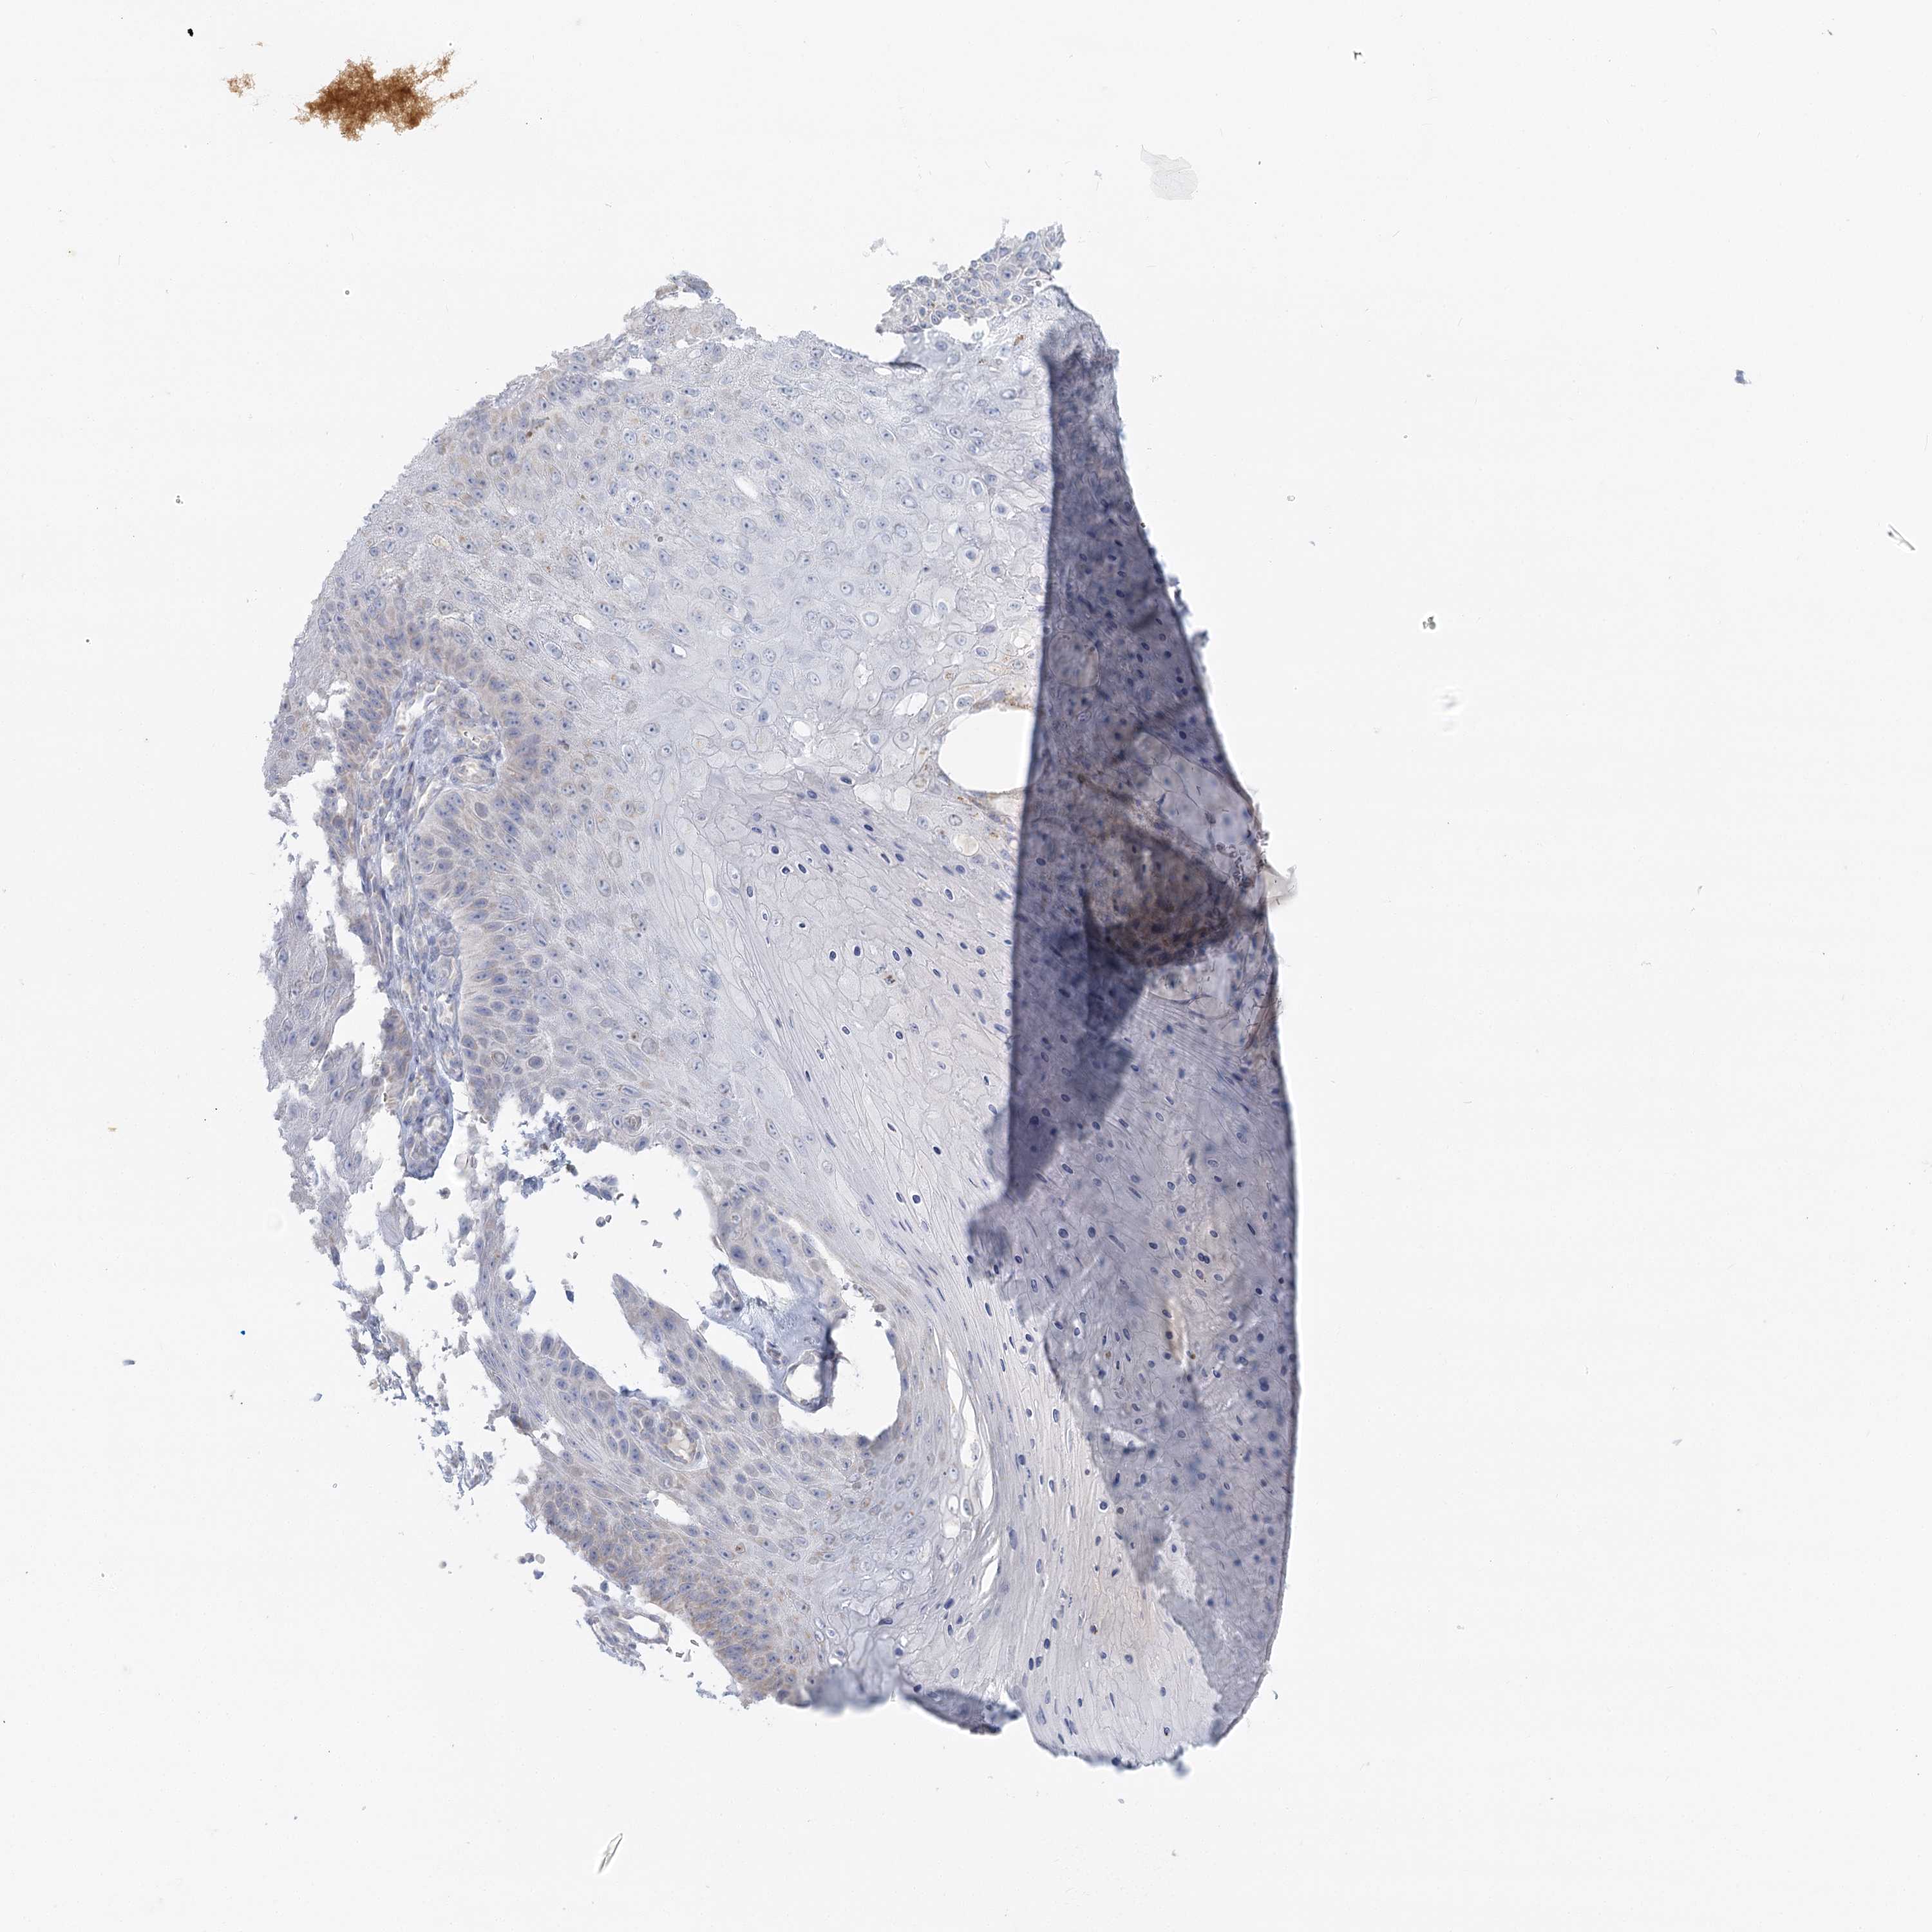

Basal cell and squamous cell cancer

SKIN CANCER - Protein expressioni

A mouse-over function shows sample information and annotation data. Click on an image to view it in a full screen mode. Samples can be filtered based on level of antibody staining by selecting one or several of the following categories: high, medium, low and not detected. The assay and annotation is described here.

Antibody stainingi

Antibody staining in the annotated cell types in the current human tissue is reported as not detected, low, medium, or high, based on conventional immunohistochemistry profiling in selected tissues. This score is based on the combination of the staining intensity and fraction of stained cells.

Each image is clickable and will lead to virtual microscopy that enables deeper exploration of all samples and also displays staining intensity scores, fraction scores and subcellular localization as well as patient and tissue information for each sample.

Antibody HPA036752

Antibody HPA036753

Staining

Not detected

Negative

None

Squamous cell carcinoma, NOS

Squamous cell carcinoma, metastatic, NOS